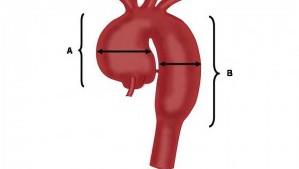

A & B

Abdominal Aorta